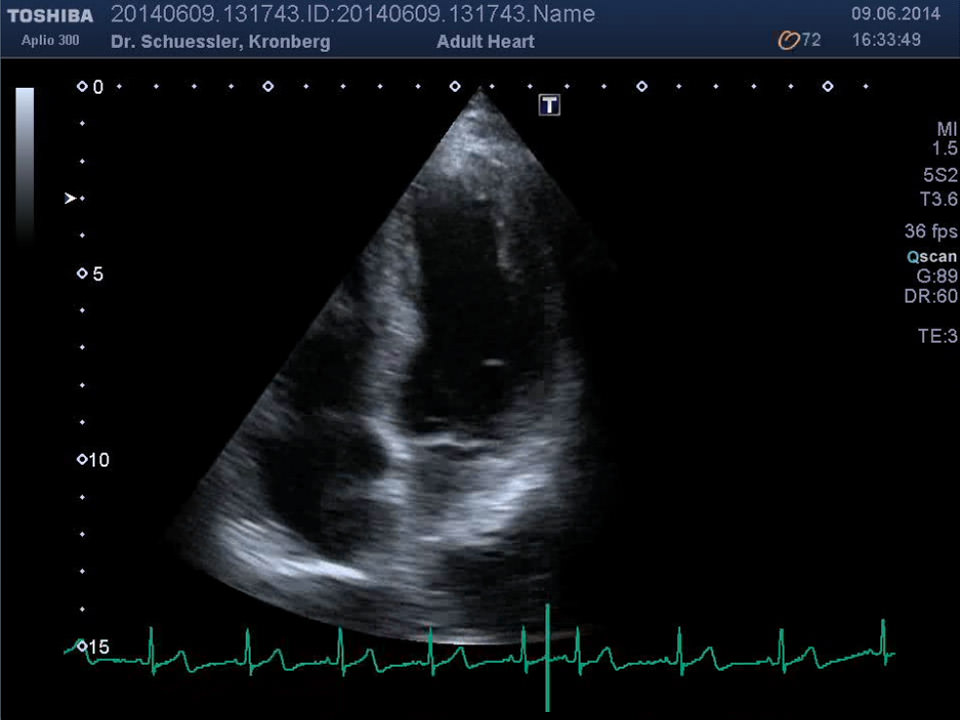

Die Ultraschalluntersuchung des Herzens erlaubt, auf einem nicht belastenden Weg, eine umfangreiche Darstellung des Herzens. Unter Hinzunahme der Farbdopplertechnik kann eine ausführliche Beurteilung der Strukturen und der Funktion des Herzens erfolgen.

Moderne Auswertungsalgorithmen wie das „Wall Motion Tracking“ erlauben eine isolierte, hochauflösende Darstellung und Analyse der Bewegung und Funktion einzelner Segmente des Herzmuskels.

• Pumpfunktion des Herzmuskels

• Segmentale Bewegungsstörungen des Herzmuskels als Hinweis auf Durchblutungsstörungen